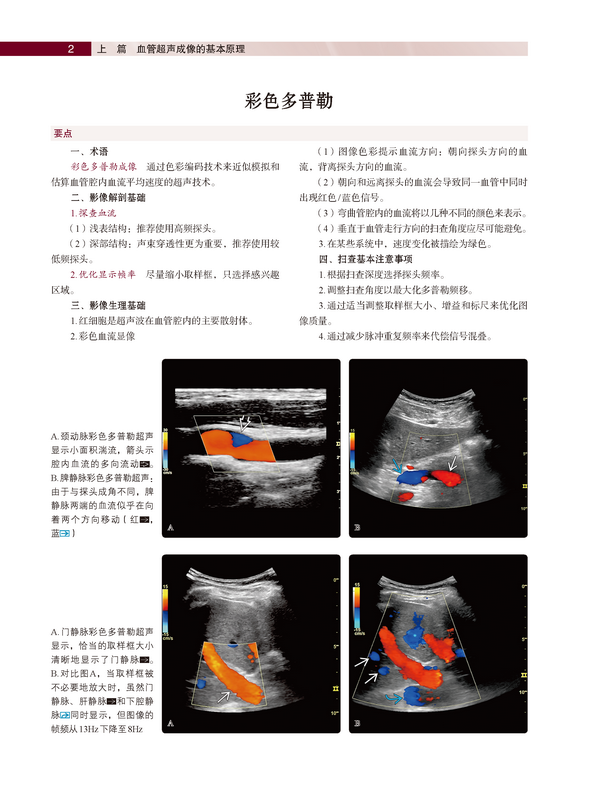

《血管超声诊断》阐述了血管超声成像的基本原理(包括彩色多普勒、能量多普勒、频谱多普勒、超声造影、微血流成像等技术);介绍了血管超声解剖基础,包括头颈部、胸部、腹部和四肢血管正常解剖及超声切面讲解、正常血管超声表现、影像成像优缺点分析;详细介绍了超声技术在血管疾病中的应用,包括血管介入治疗术前超声评估,手术流程标准化、规范化操作,术后并发症的诊断及超声表现等。《血管超声诊断》的一大特色是对每一章节内容均进行了简要总结列在文前,此外,小标题和亚标题的使用令阅读和查询更加便捷,方便读者能够迅速、准确地获取知识点。正文按照大体解剖学、影像解剖学、成像建议(部分章节涉及胚胎学)进行详细介绍。《血管超声诊断》的另一特色是每章节之后都配有丰富翔实、高清晰度的解剖及影像学彩色图谱,对脏器血管全方位、立体化展示,帮助初学者快速掌握血管正常结构及常见疾病的超声表现。